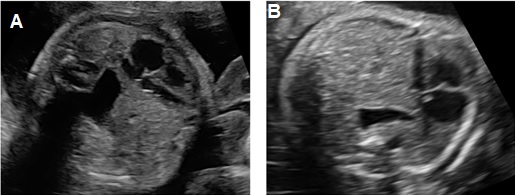

Thoát vị hoành trái: Ở mặt cắt ngang 4 buồng tim có khối phản âm không đồng nhất ở trong lồng ngực trái có thể là dạ dày chứa dịch bên trong (+/-) ruột, gan. Trung thất và tim bị đẩy lệch qua bên phải (Dextroposition). Ở mặt cắt ngang bụng không thấy dạ dày nếu đã bị thoát vị lên lồng ngực.

Thoát vị hoành phải nếu chỉ đơn thuần gan lên có thể khó nhận diện vì phản âm của gan tương tự phổi trên siêu siêu âm thang xám. Hình ảnh đường mật, túi mật là đặc trưng giúp nhận diện gan. Doppler màu có gía trị vì giúp nhận diện các tĩnh mạch gan. Dấu hiệu gián tiếp có thể thấy là hình ảnh trục tim bị lệch.

Hình 2. Thoát vị hoành trái. A: Mặt cắt ngang bụng không thấy dạ dày. B: Mặt cắt ngang 4 buồng tim có hình ảnh dạ dày (DD) và ruột đẩy sát tim qua sát thành ngực phải; phổi phải bị chèn ép.